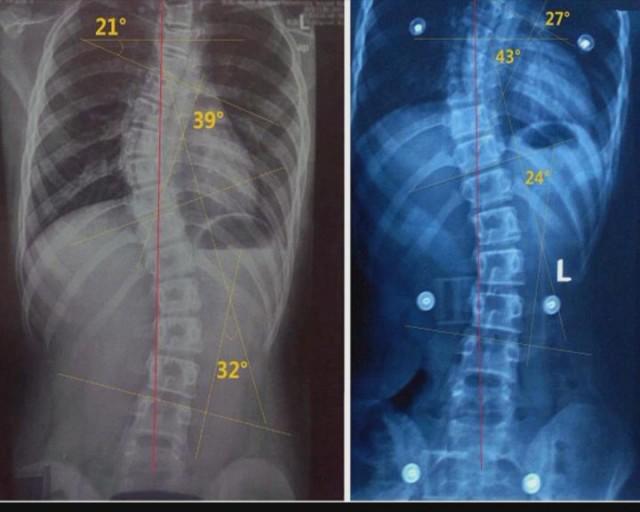

如果发现走路时跛行。外观从正面看有双肩不等高或肩胛骨一高一低,一侧胸部出现褶皱皮纹,后背看有背部一侧隆起畸形。甚至有些出现“漏斗胸”或“鸡胸”畸形,患者双手合十向前弯曲,检查者从后方看患者背部发现不对称。那么应怀疑有“脊柱侧凸”。这个时候应拍摄站立位的全脊柱X线片,如果正位X线片显示脊柱有大于10度的侧方弯曲,即可诊断为脊柱侧凸。轻度的脊柱侧凸通常没有明显的不适,外观上也看不到明显的躯体畸形,特别是穿衣时。有的脊柱侧凸则会影响婴幼儿及青少年的生长发育,使身体变形,严重者可以影响心肺功能、甚至累及脊髓,造成瘫痪。发现轻度的脊柱侧凸可以先到专业的机构学习一些关于对脊柱侧凸训练方法,比如矫正操、瑜伽、燕子飞、游泳等。一般大于20度小于40的脊柱侧凸则需要佩戴矫形支具,一般每天佩戴至少20-22小时,剩余时间配合一些对于加强腰背肌肉的锻炼,脊柱功能的训练,从而降低需要手术的概率。一般超过40度以上则需要手术干预治疗。任何脊柱侧凸不管严重程度都是需要适当的干预。并定期到医院复查,注意脊柱侧凸的度数。脊柱侧凸是危害青少年和儿童的常见疾病,关键是要早发现、早治疗。

对于脊柱侧弯目前国际上比较有效的治疗方法只有两种,一种是矫形支具治疗加锻炼,一种是手术治疗。矫形支具是一个比较专业的治疗,是需要到医院或者到专业的机构做,是需要用石膏取模,再把这个石膏模送到工厂来做,它是对身体有针对性的支具。支具的原理也是比较简单,他就是通过挤压肋骨的方式,三点加压,每天至少佩戴20-22小时,才能达到矫正作用,半年到一年跟换一次。佩戴支具应在一小时后拍片子看看支具是否达到所需要的矫正需求。复查拍片时应提前四小时以上脱掉支具。支具治疗适用于16岁以下的,主要是用于青少年。脊柱侧弯手术现在国内比较成熟,常用得设备有两个,术中导航、神经监护。一般手术医生会挑一个。这两个设备主要是用于钛合金支架置入螺钉操作时用。术后搬运患者到病床时,注意保持脊柱水平位,平托到床边。患者卧硬床板,全麻清醒,平卧6小时后可以进行翻身,翻身幅度不能太大。术后3-7天天左右可以佩戴支具保护逐渐下地行走(具体看主治医生要求)。起初第一次坐起来,往往会有头晕不适等,需要有人陪护下做起,逐步在床上多练习几次坐起之后,可以练习站立,如果站立时没有不适,则可以在室内尝试下地活动,自己去洗手间。